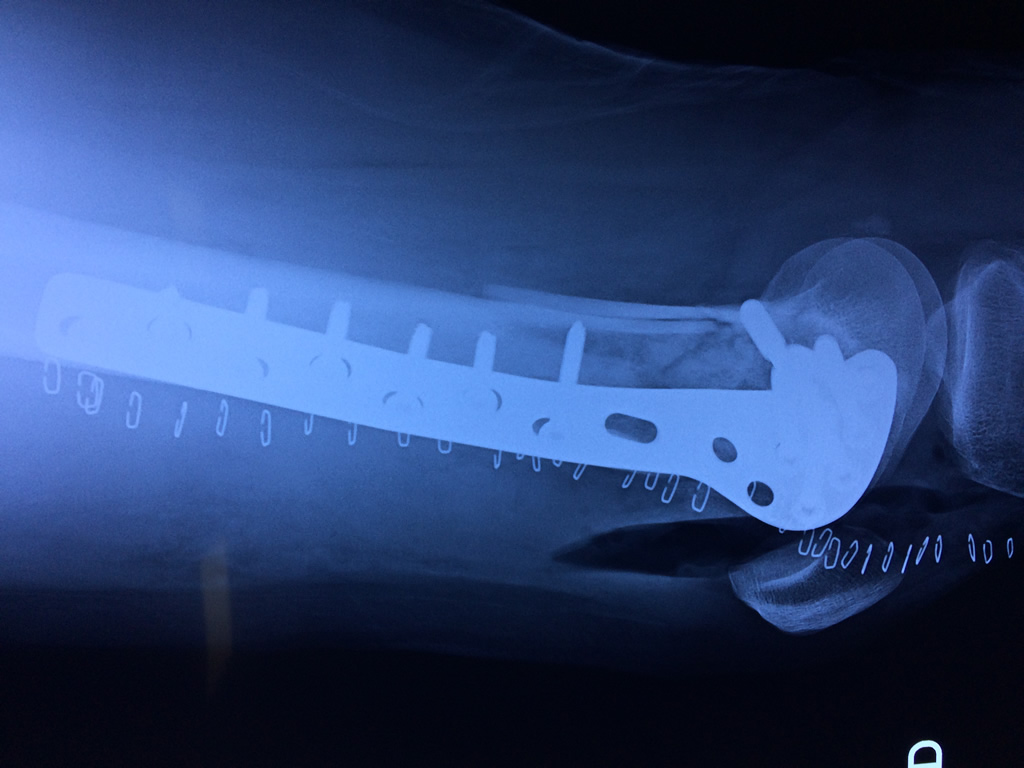

Cirugías de Codos - Fémur

El fémur es el hueso del muslo, el segundo segmento del miembro inferior. Es el hueso más largo, fuerte y voluminoso del cuerpo humano.